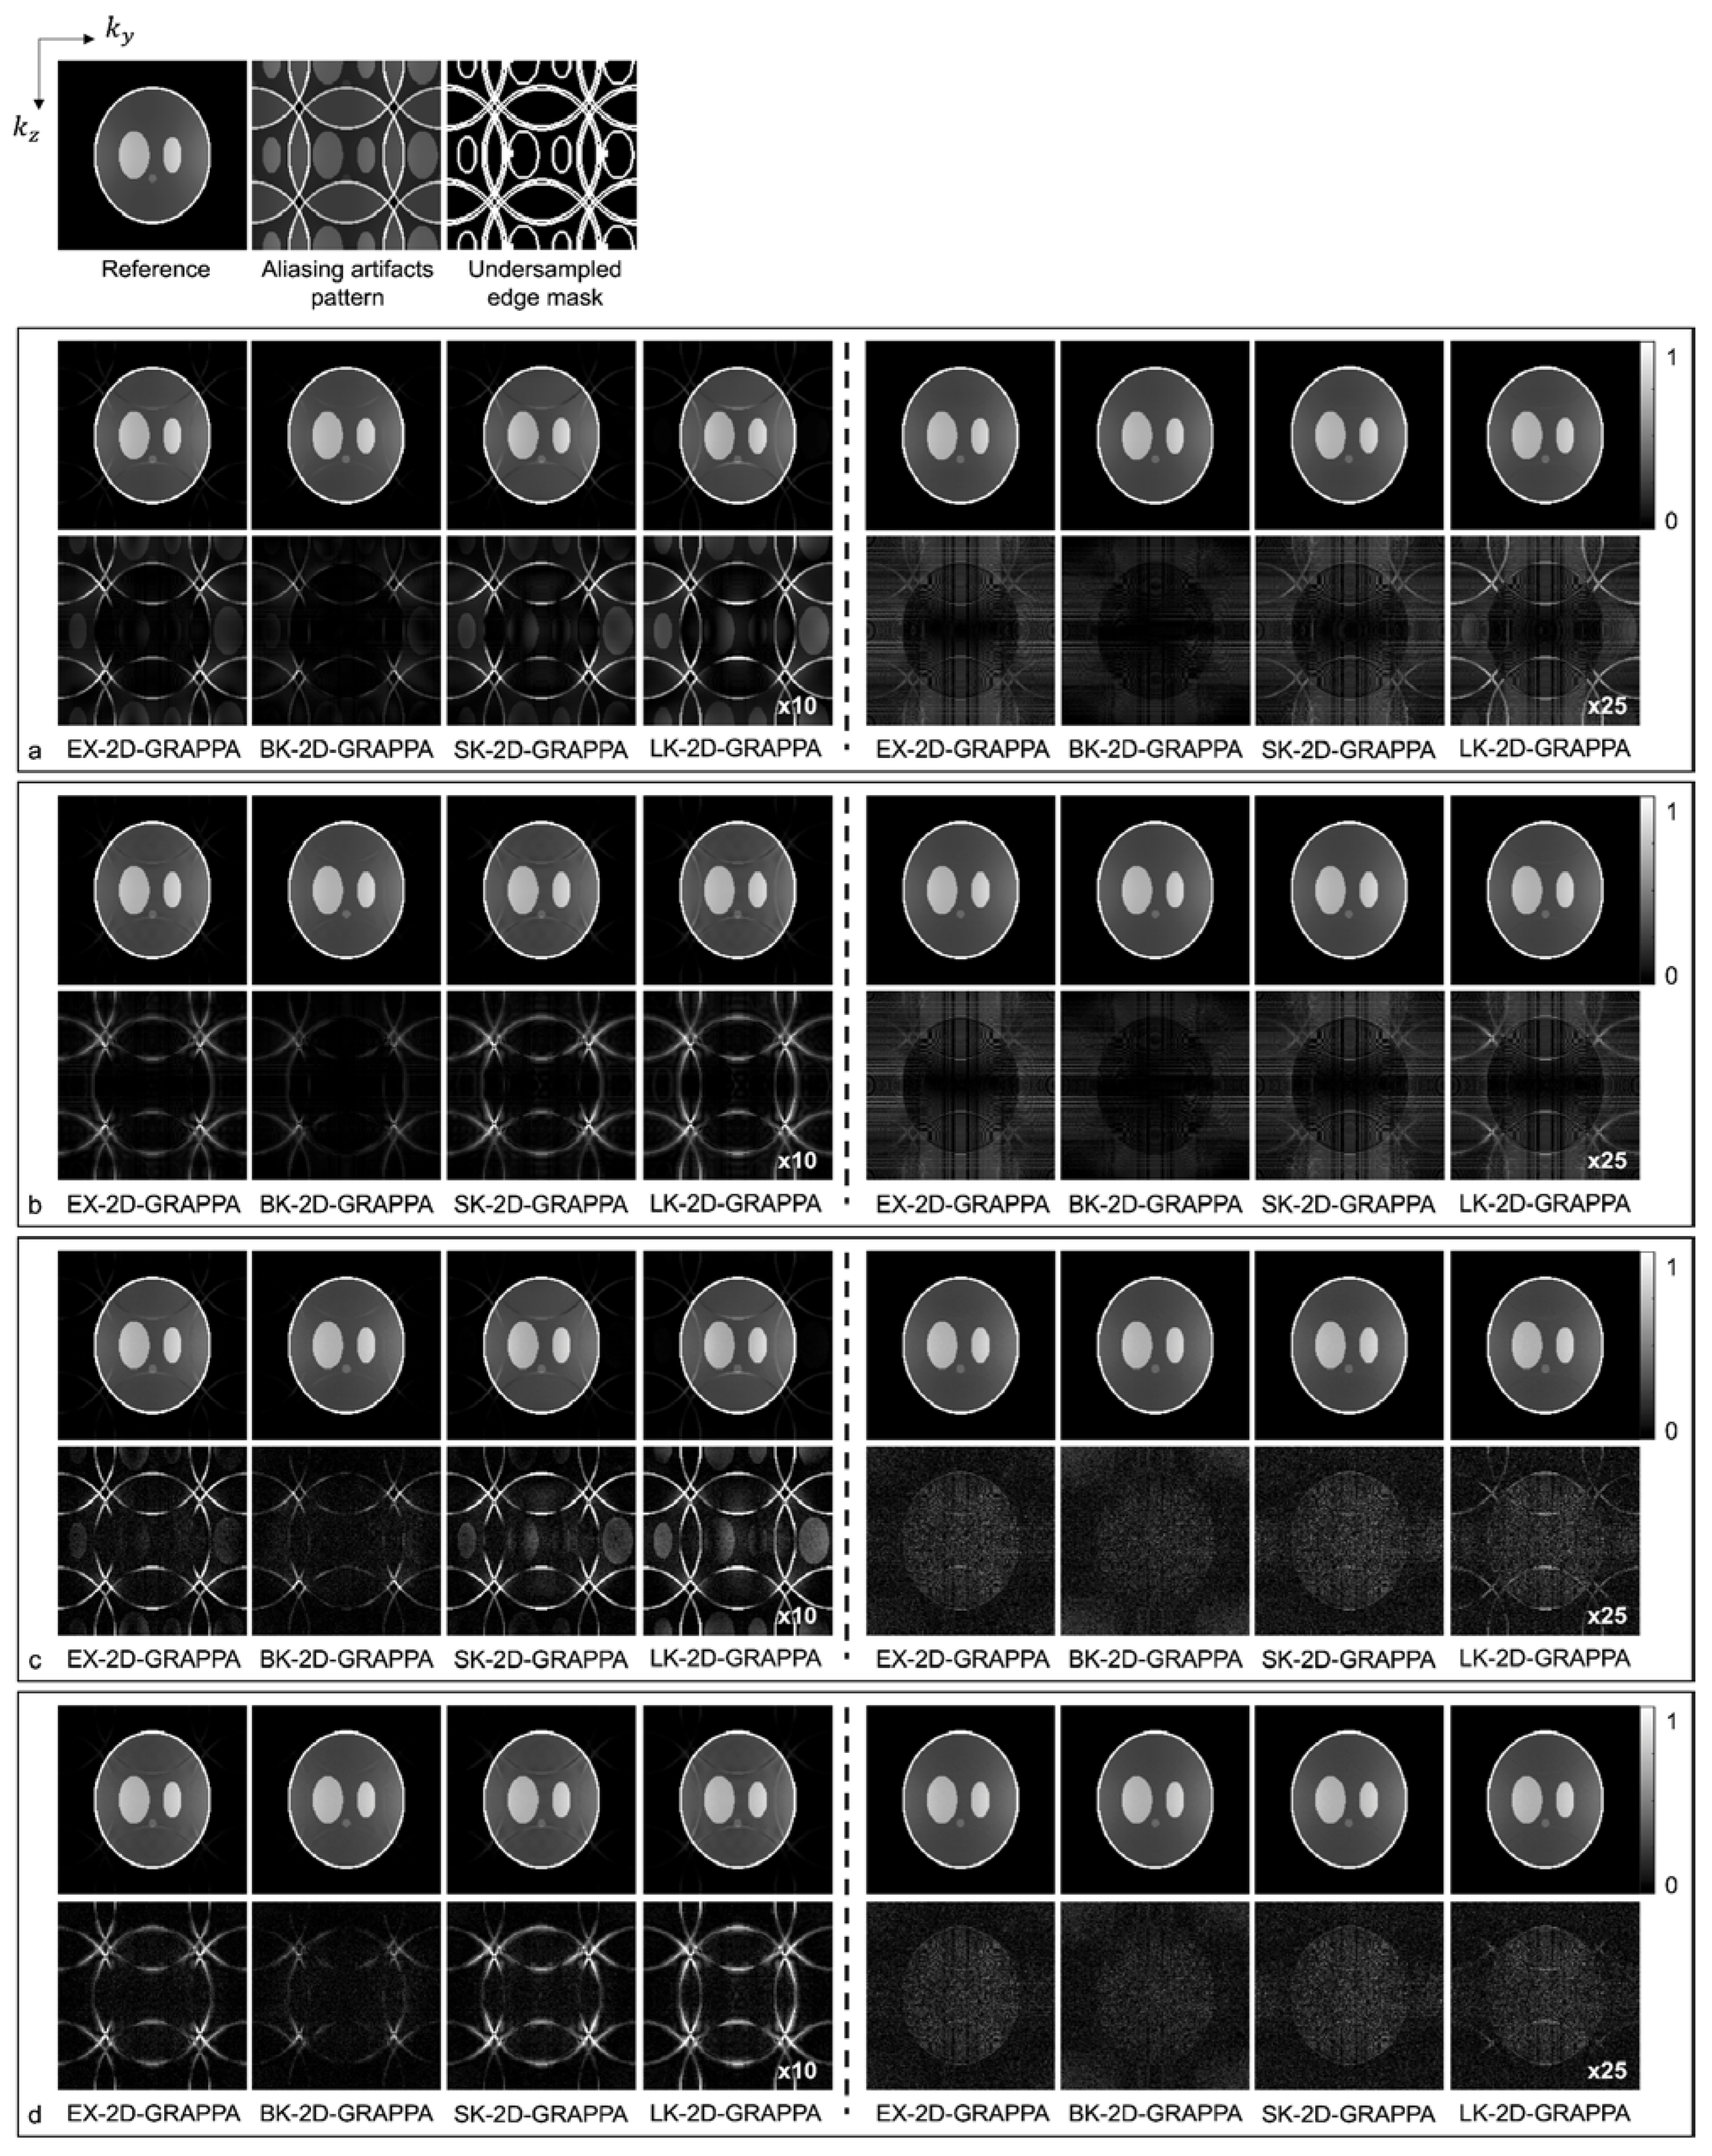

4. Results